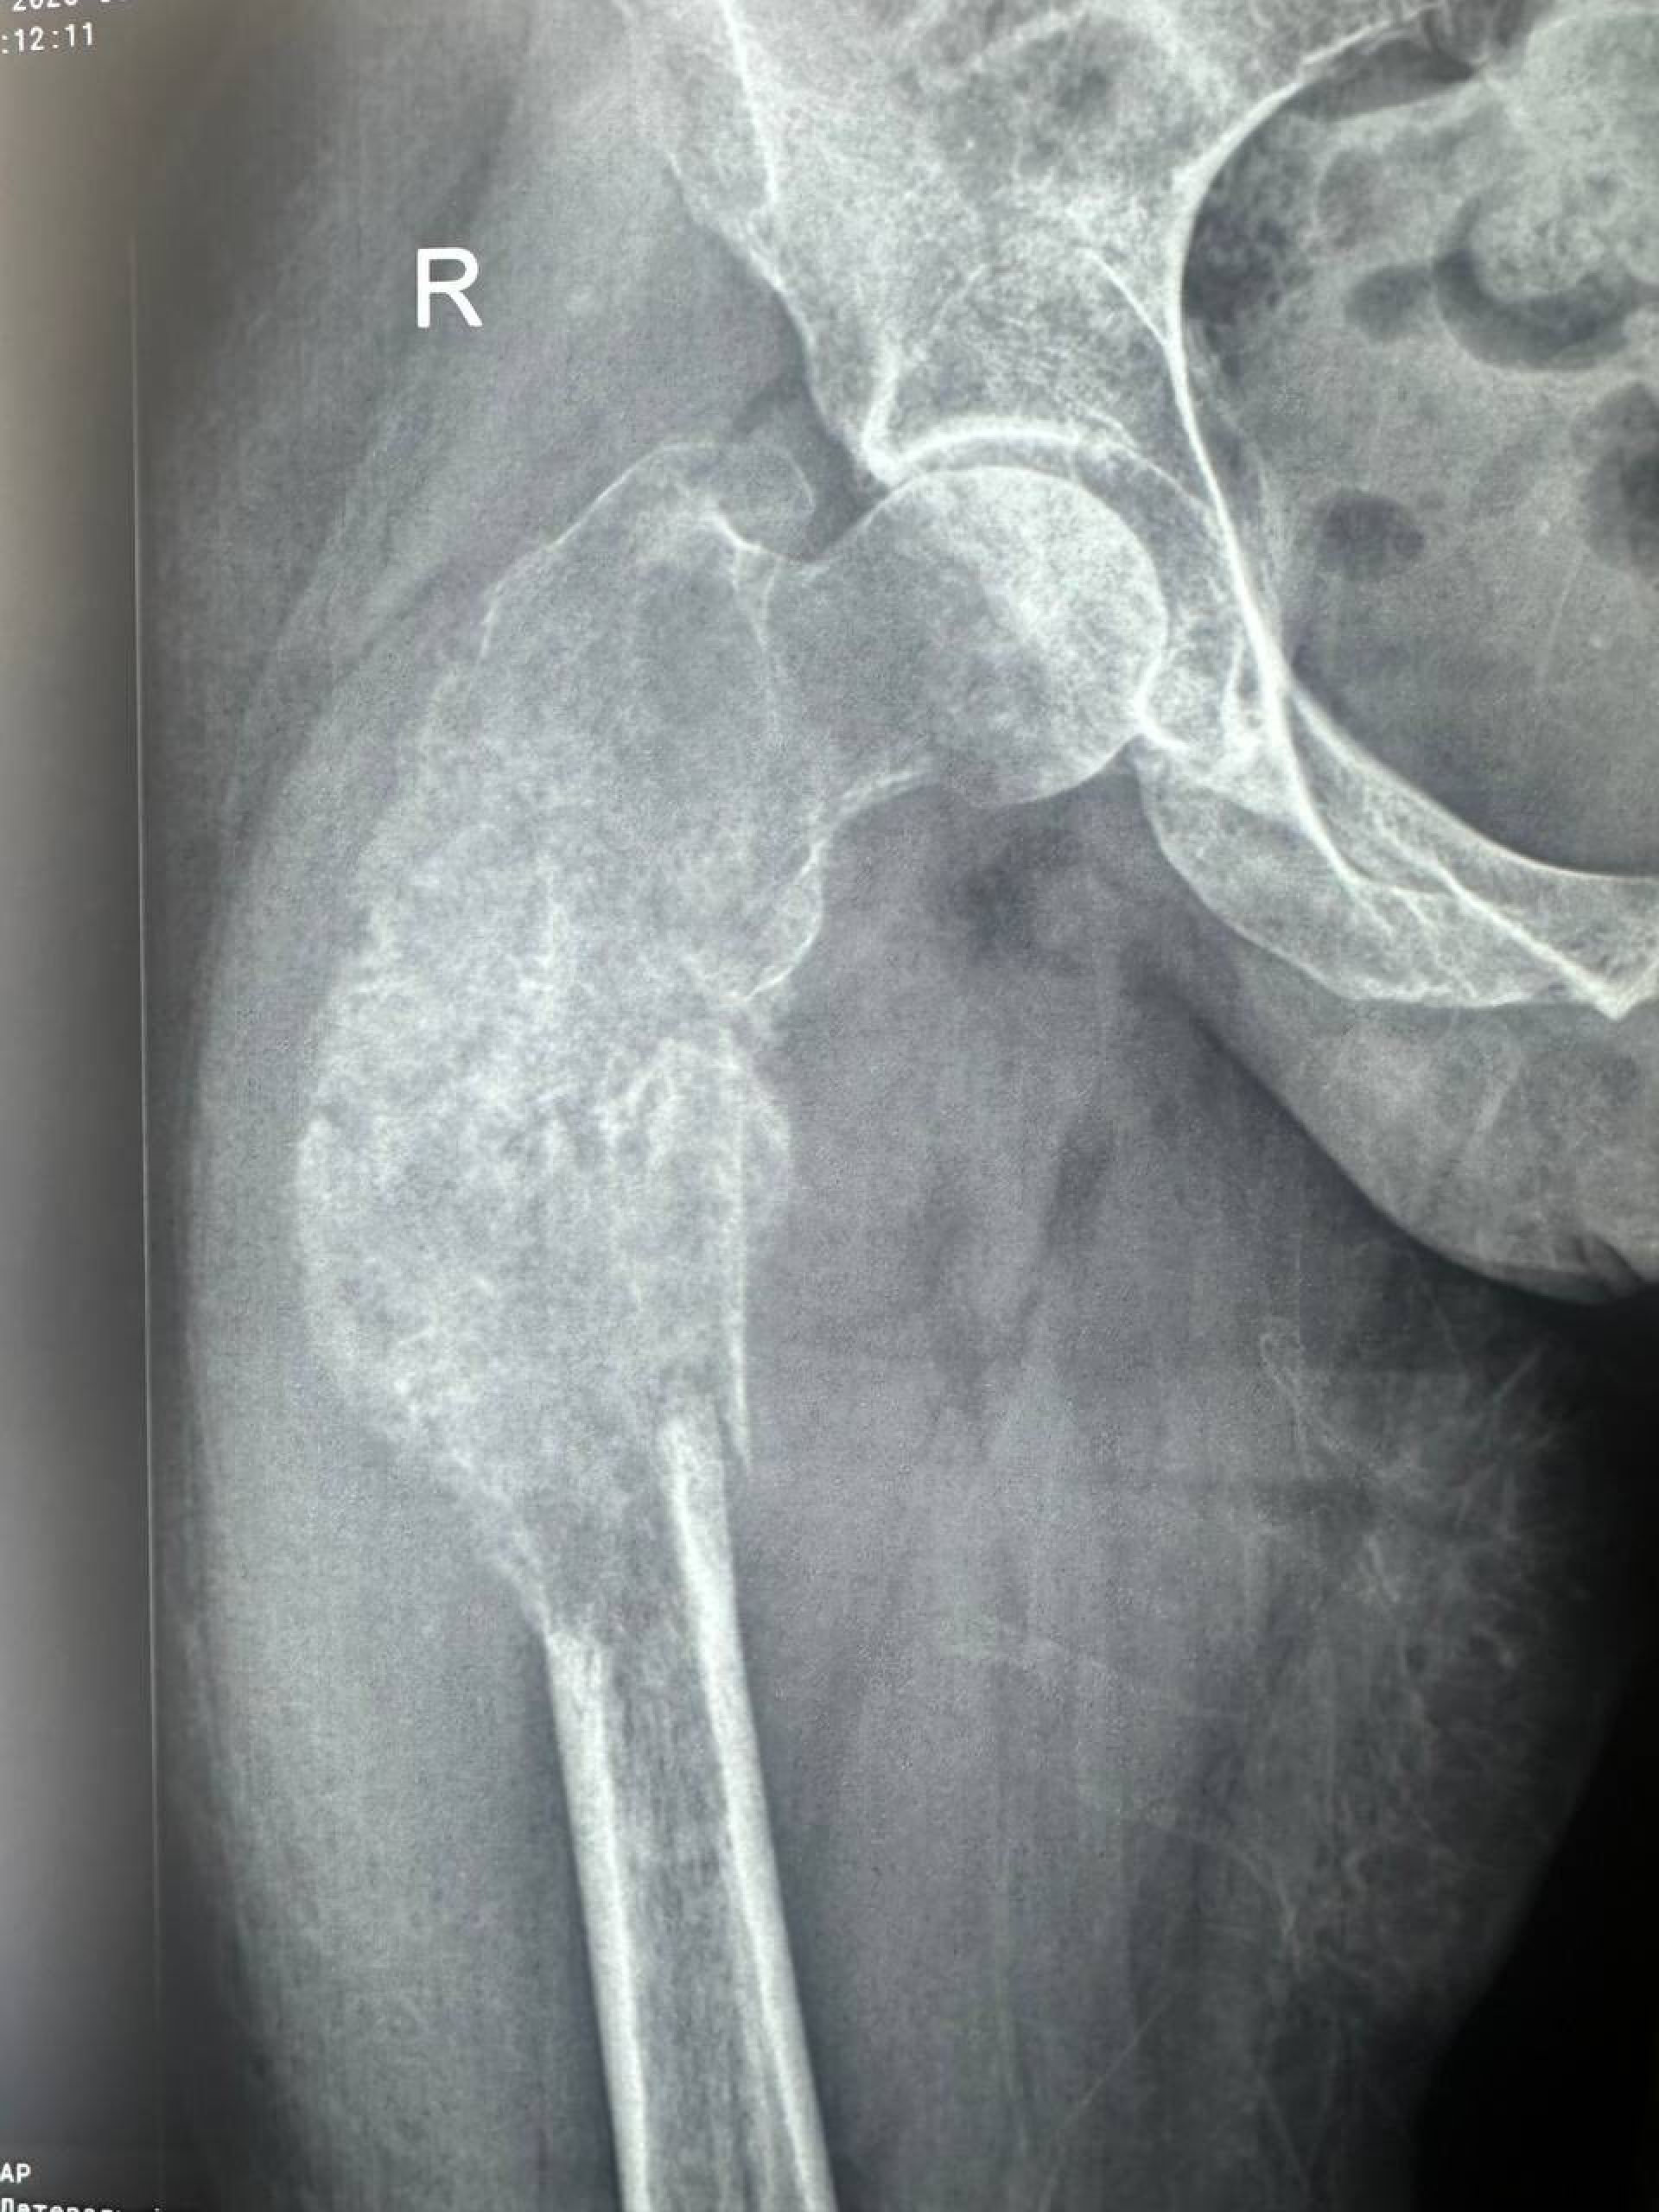

- Її мама має важку недугу — рак легень з метастазами (аденокарцинома). Хвороба вразила легені, печінку, лімфовузли та кістку.

— Ніколи не думала, що доведеться писати такий пост… Моя мама, Світлана Стойко Svetlana Stoyko, зараз бореться з дуже важким діагнозом — рак легені з метастазами (аденокарцинома). Хвороба вразила легені, печінку, лімфовузли та кістку. Нещодавно стався страшний момент — через ураження кістки метастазами в мами трапився патологічний перелом стегна. Зараз вона прикута до ліжка і відчуває сильний біль… — пише Вероніка

За словами Вероніки, є шанс допомогти. Лікарі готові провести операцію з ендопротезування кульшового суглоба та частини стегнової кістки, щоб мама могла знову ходити та продовжувати лікування. Але для цього потрібно 400 000 грн: 200 тисяч ціна операції, близько 3,5 тисяч євро протез і 50 тисяч на реабілітацію після операції